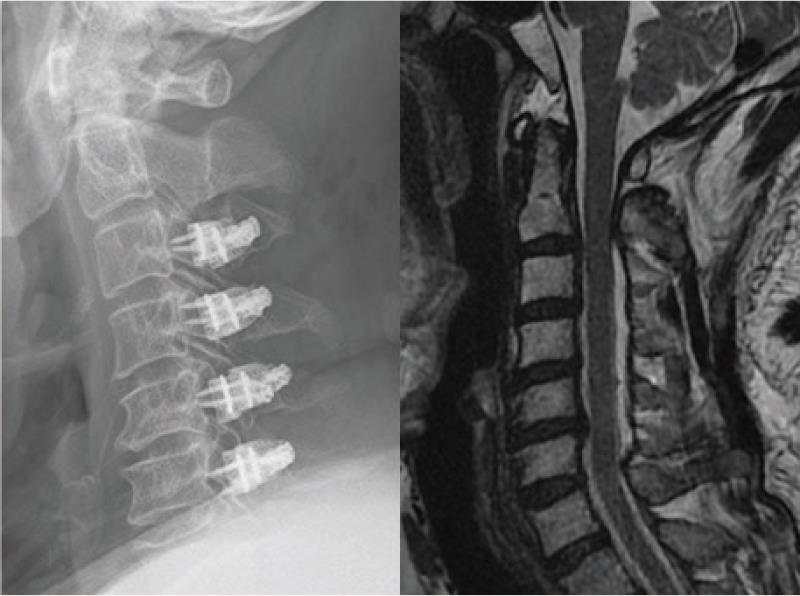

病例3:颈后路保留后方肌肉韧带复合体的单开门椎管扩大成形术

脊髓型颈椎病,术前X线和核磁示多节段椎间盘突出

颈后路保留后方肌肉韧带复合体的单开门椎管扩大成形术,术后随访示椎管扩大良好。